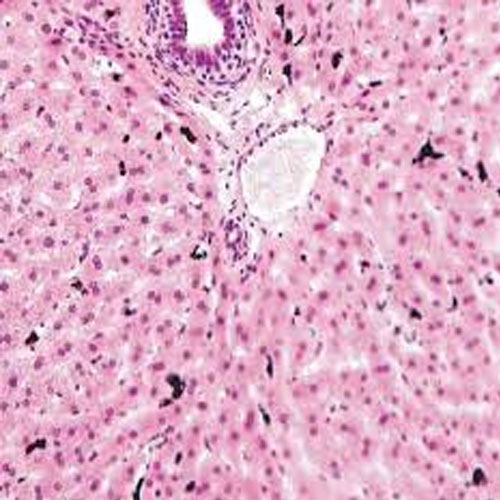

Bir deney hayvanına karbon partikül içerikli vital boya uygulamasından beş saat sonra karaciğerden alınan doku kesiti, hematoksilen-eozin ile boyanıp ışık mikroskobunda inceleniyor. (Atom ağırlıkları; C=12,0 g/moL, H=1,0 g/moL, O=16,0 g/moL, N=14,0 g/moL)

Cevap: B) Kupffer hücresi Açıklama: Kupffer hücreleri, karaciğerin makrofajlarıdır ve karaciğerin sinüzoidlerinde bulunurlar. Vital boya ile uygulanan karbon partiküllerini fagosite etme özellikleri sayesinde, bu hücreler mikroskop altında siyah renkte görünür. Karbon partiküllerini yakalayıp sindiren Kupffer hücreleri, bu nedenle deneyde siyah renkte görülen hücrelerdir. Bu özellik, onları diğer hücrelerden ayırt etmeyi sağlar.